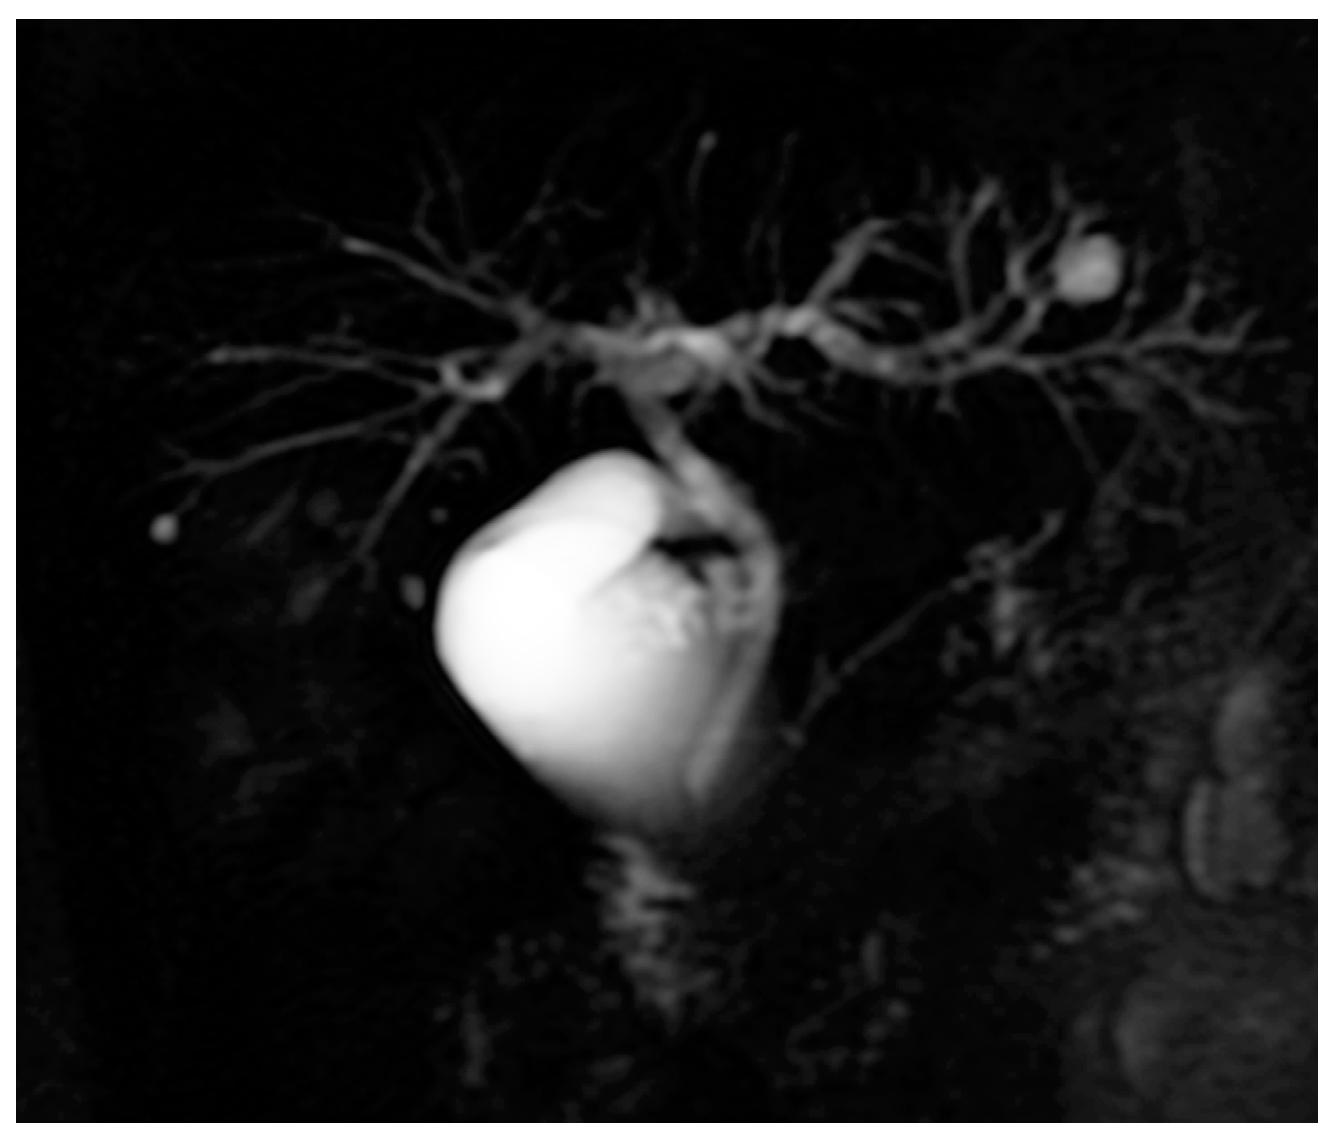

2.2. Case 2